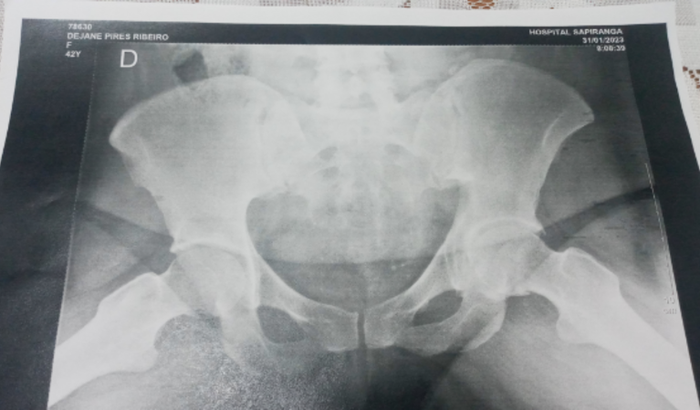

A exatamente 22 anos e 6 meses atrás, eu (gestante de 8 semanas) e meu esposo, estávamos passeando por volta das 22H pelo bairro proximo de nossa casa. E veio em nossa direção uma combi e o motorista que estava alcoolizado, nos atropelou. Meu esposo teve ferimentos leves, mas eu fraturei o quadril, bacia, fémur, e trauma contuso do braço esquerdo. No momento ele não nos prestou ajuda nenhuma! (Até hoje NUNCA)

Mas com a gestação inteira sem os medicamentos necessários, ao invés do osso do quadril( femur) ficar no lugar, com o tempo foi desgastando, hoje tem um nome especifico para isso: artropatia degenerativa, e entre todos esses anos, muitas vezes fiquei enconstada tomando medicações fortes e com alto custo. Ou trabalhei com dores da mesma forma, pois sempre tentei fazer de tudo pelas minhas filhas.